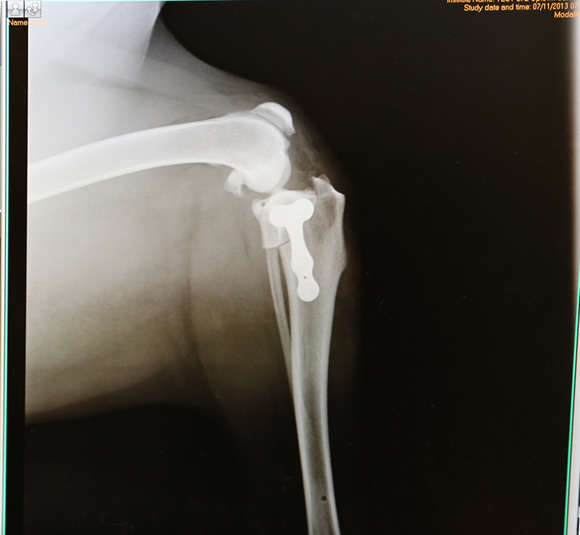

• Tibial Plateau Leveling Osteotomy TPLO

ball-implant-tplo-580

• ball-implant-tplo-580